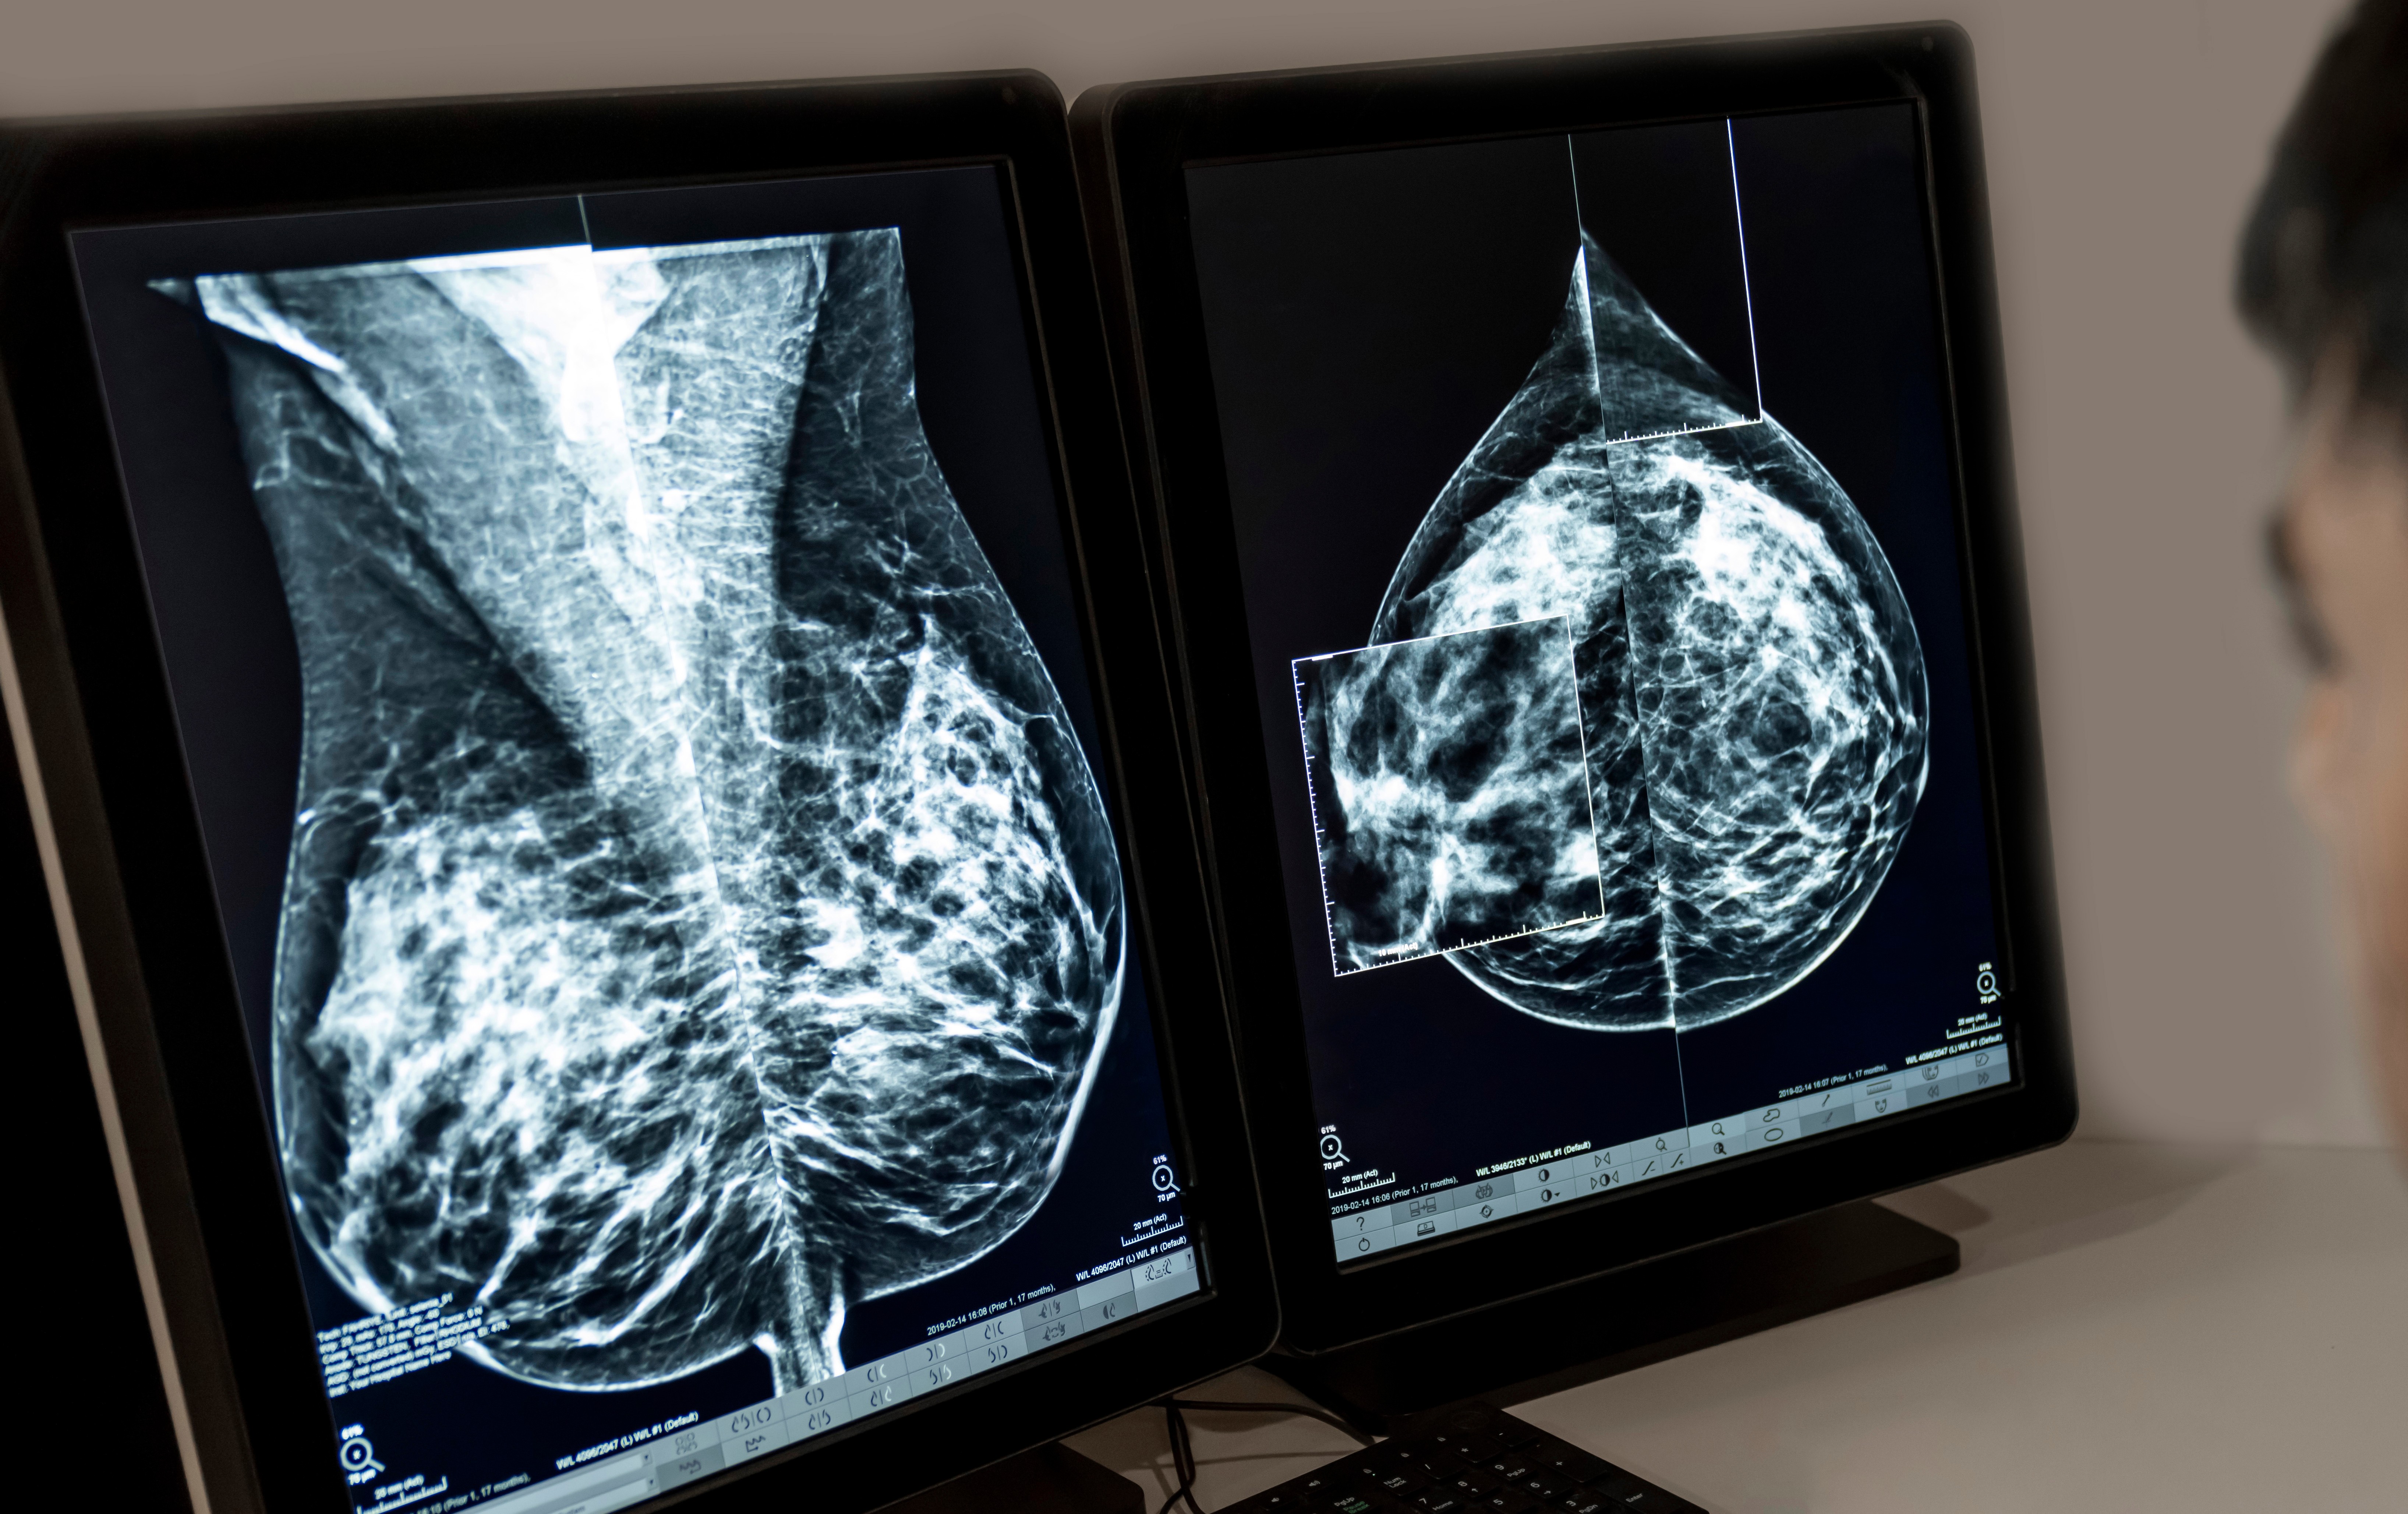

RJ tem a segunda maior mortalidade por câncer de mama no país, diz Inca

03/10/2025 - Segundo o Inca, o RJ tem a segunda maior mortalidade por câncer de mama no país

O Estado do Rio de Janeiro possui a segunda maior taxa de mortalidade de mulheres vítimas de câncer de mama por 100 mil habitantes no país com 16,5 casos. Os dados, referentes ao ano de 2023, foram divulgados nesta sexta-feira (3) pelo Instituto Nacional do Câncer, durante o lançamento da campanha Outubro Rosa. Roraima lidera o ranking de mortalidade.

O número de casos registrados no RJ também é o segundo maior do país, com 70,57 casos de câncer de mama por 100 mil habitantes entre 2023 e 2025. O maior número é de Santa Catarina.

“É fundamental investirmos na prevenção. Controle de peso, evitar tabagismo e consumo de álcool. E é importante o rastreio entre mulheres entre 50 e 74 anos de idade e podendo ser oferecido para mulheres com idade entre 40 e 49 anos”, afirmou Braga.

“Hoje temos menos de 30% das mulheres em idade alvo ainda fazendo a sua mamografia a cada dois anos entre 50 e 74 anos de idade, mostrando que uma parte ainda não consegue fazer a mamografia”, disse o coordenador.